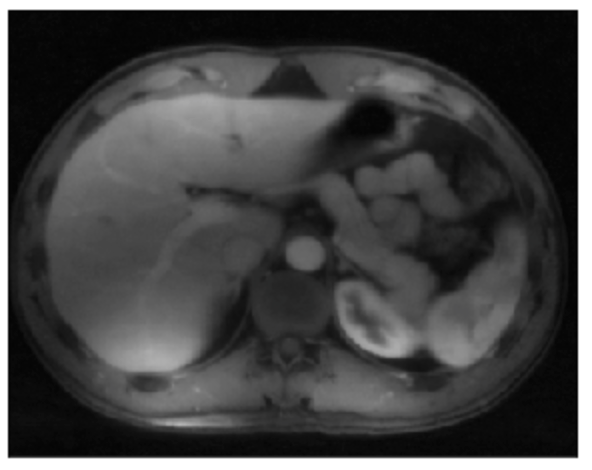

Refer to caption

(a) Noisy image of a chest scan.

(b) Posterior Fréchet mean corresponding to a piece-wise constant smoothing.

(c) Pixel-wise probability for each pixel being not equal to at least one of the neighboring pixels.

Figure 3: An example of the sparse contrast modeling using the generalized l1subscript𝑙1l_{1}-ball prior. Our model finds a piece-wise constant smoothing (b) underneath a noisy image (a), while quantifying the uncertainty (c).

We apply the above model with a generalized l1subscript𝑙1l_{1}-ball prior using βi,jiidDE(0,1)superscriptsimilar-toiidsubscript𝛽𝑖𝑗DE01\beta_{i,j}\stackrel{{\scriptstyle\text{iid}}}{{\sim}}\text{DE}(0,1), and α=10.𝛼10\alpha=10.. The scan image is from Gong et al. (2017) and previously used by Xu and Fan (2021), with the noisy raw data plotted in Figure 3(a). In the posterior samples, the Fréchet mean indeed recovers a segment-wise constant structure, with each part clearly shown (b). Importantly, we quantify the posterior probability that a smoothed pixel is not equal to at least one of its neighbors, pr[θi,jθ(i+k,j+k) for at least one (k,k)=(0,1),(1,0),(1,0),(0,1)y]\text{pr}[\theta_{i,j}\neq\theta_{(i+k,j+k^{\prime})}\;\text{ for at least one }(k,k^{\prime})=(0,1),(1,0),(-1,0),(0,-1)\mid y] for i=2,,p1𝑖2𝑝1i=2,\ldots,p-1 and j=2,,p1𝑗2𝑝1j=2,\ldots,p-1. Indeed, those large probabilities are located near the boundary; and interesting extension could be further explored, such as one for Bayesian multiplicity control on image boundary detection.